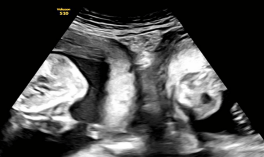

孕21周🔼